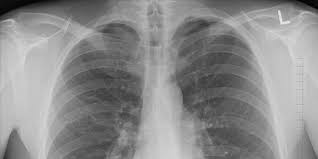

وأظهرت الفحوصات الطبية إصابته بفشل رئوي حاد ناتج عن التهاب القصيبات الانسدادي، وهو مرض يُعرف شعبياً بـ”رئة الفشار”، ما استوجب تزويده بالأوكسجين بشكل دائم، حتى أثناء ذهابه إلى المدرسة.

الدكتور همام الشققي، استشاري طب الرئة، أوضح في حديث لـ”سكاي نيوز عربية” أن “رئة الفشار” هي حالة طبية خطيرة ناتجة عن التعرض لمادة كيميائية تُعرف باسم “دي أستايل” (Diacetyl)، والتي تُستخدم في نكهات بعض أنواع الفيب، وقد ارتبطت سابقًا بإصابة عمال مصانع الفشار بهذا المرض.

“ما يجعل الأمر خطيرًا هو أن هذه المادة تدخل مباشرة إلى الرئتين وتسبب التهابات شديدة وتلفًا دائمًا في الشعب الهوائية”، أضاف الدكتور الشققي.